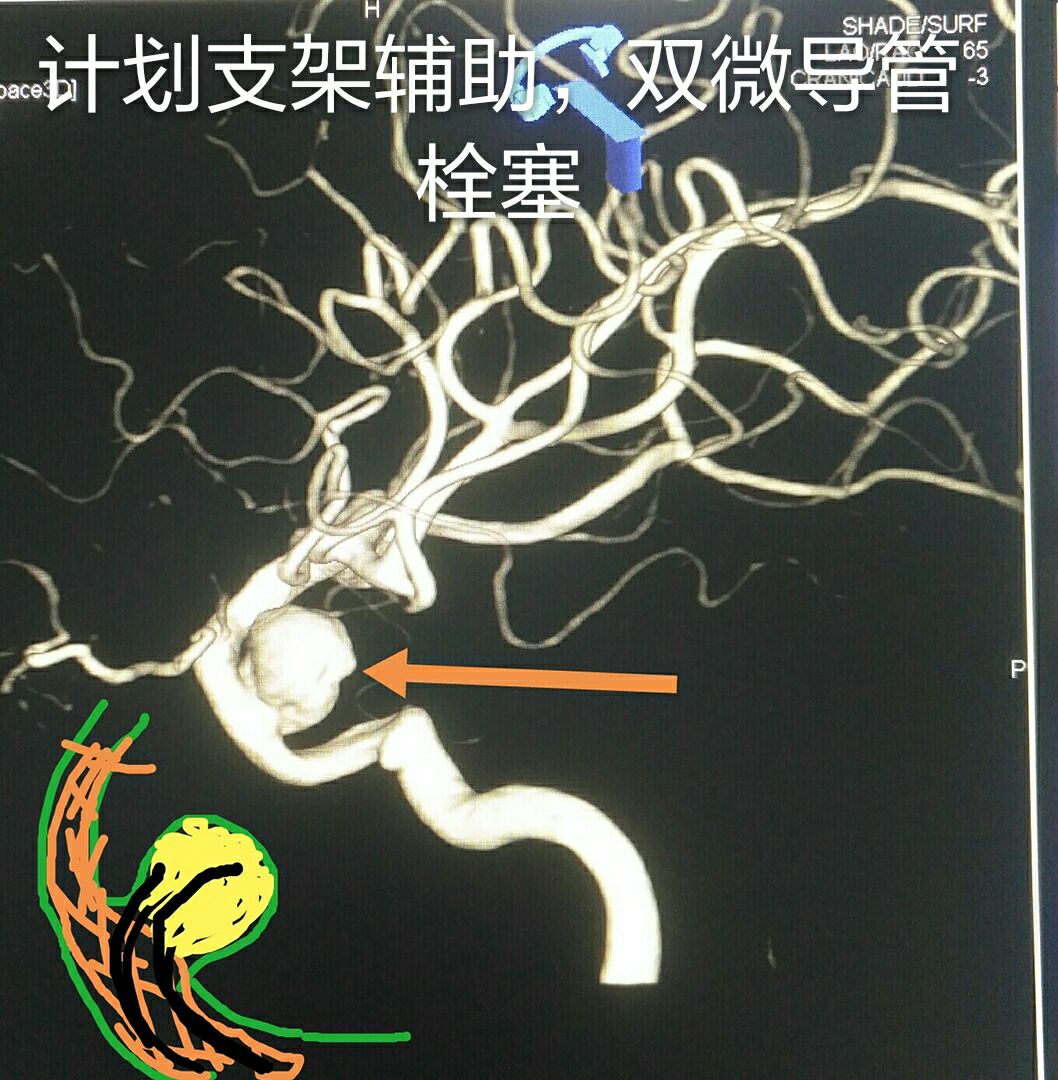

病例一:左侧颈内动脉虹吸弯大动脉瘤,宽颈,形态不规则

支架辅助+双微导管技术致密栓塞动脉瘤